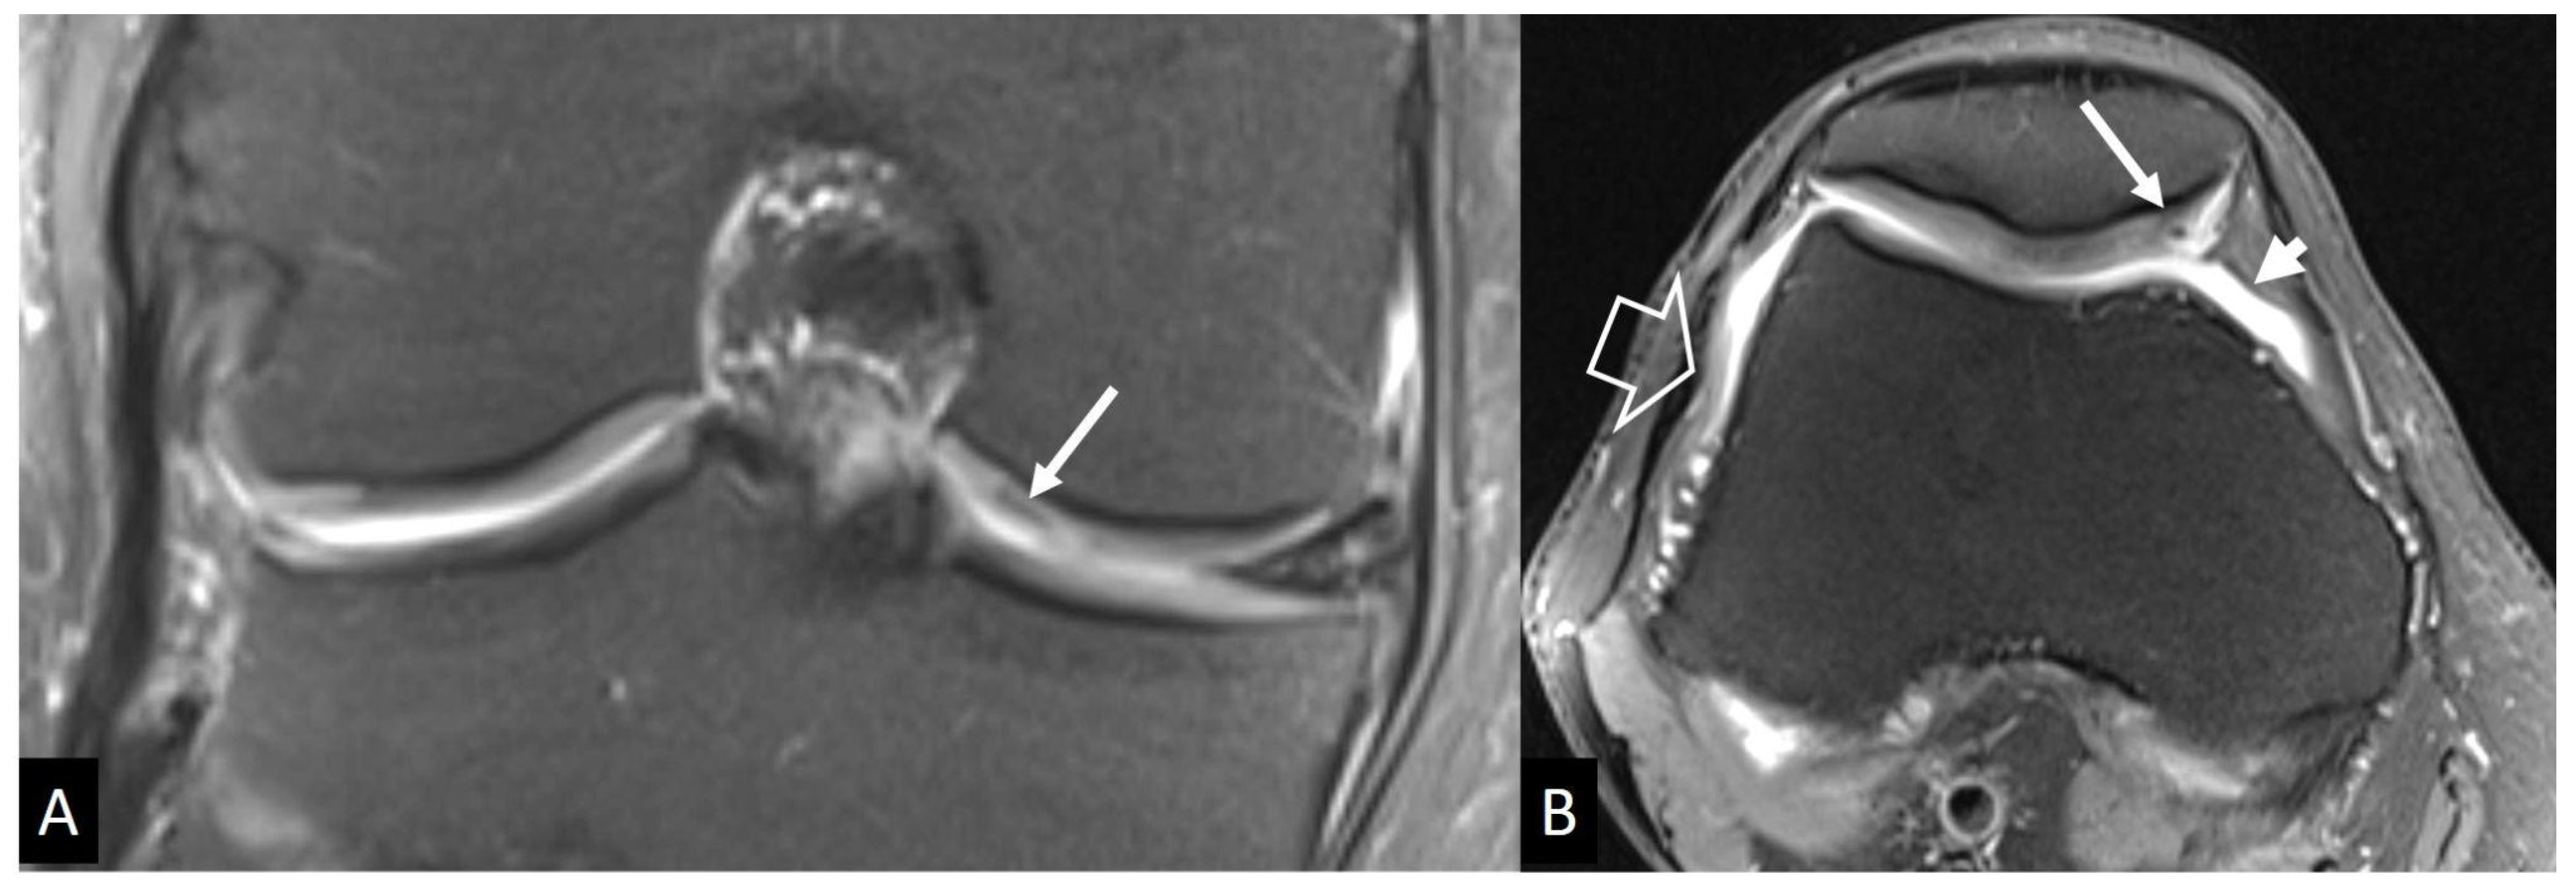

4.2.2. Neuropathic Arthropathy

4.2.3. Crystal-Induced Arthropathies